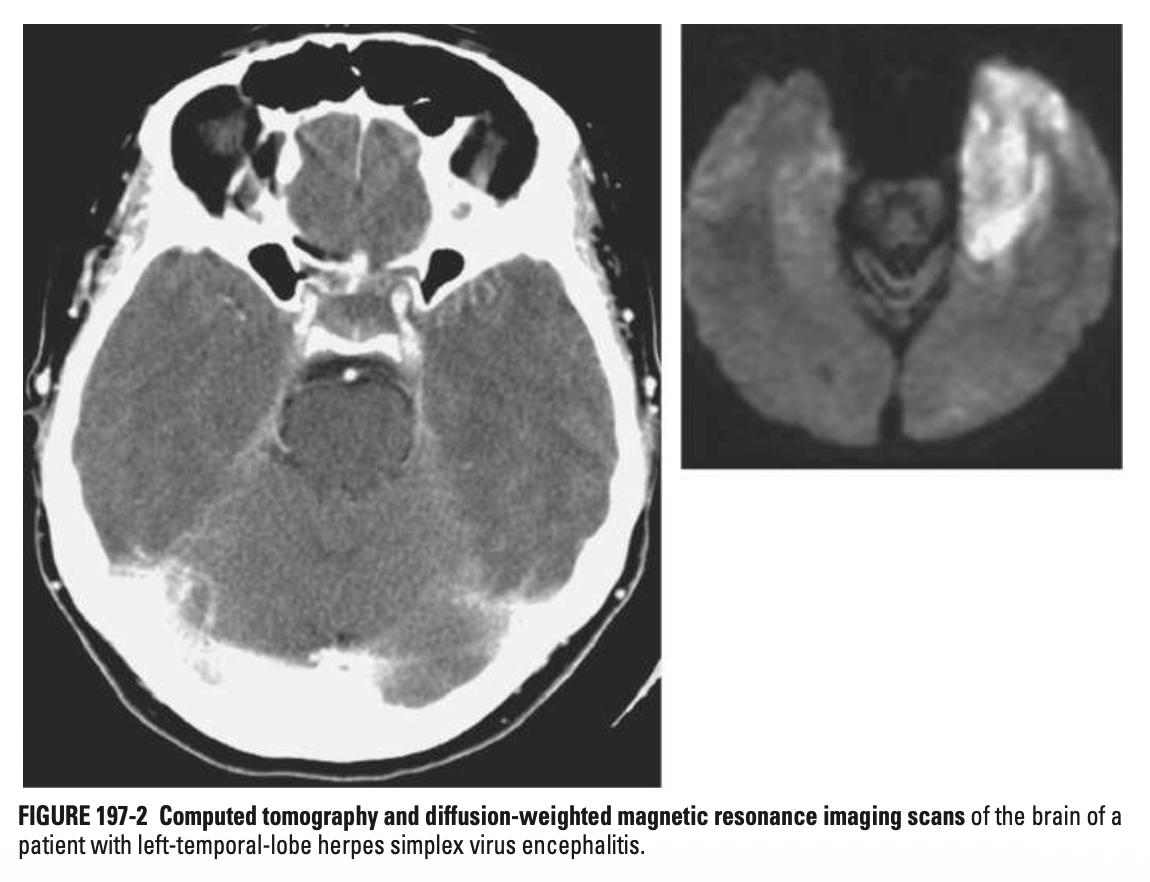

• HSV 뇌염 (Encephalitis): 주로 HSV-1, 측두엽(Temporal lobe) 침범 (MRI상 특징적), 발열/두통/의식저하/성격변화

[1] Harrison 22e. Chapter 197, Herpes Simplex Virus Infections.